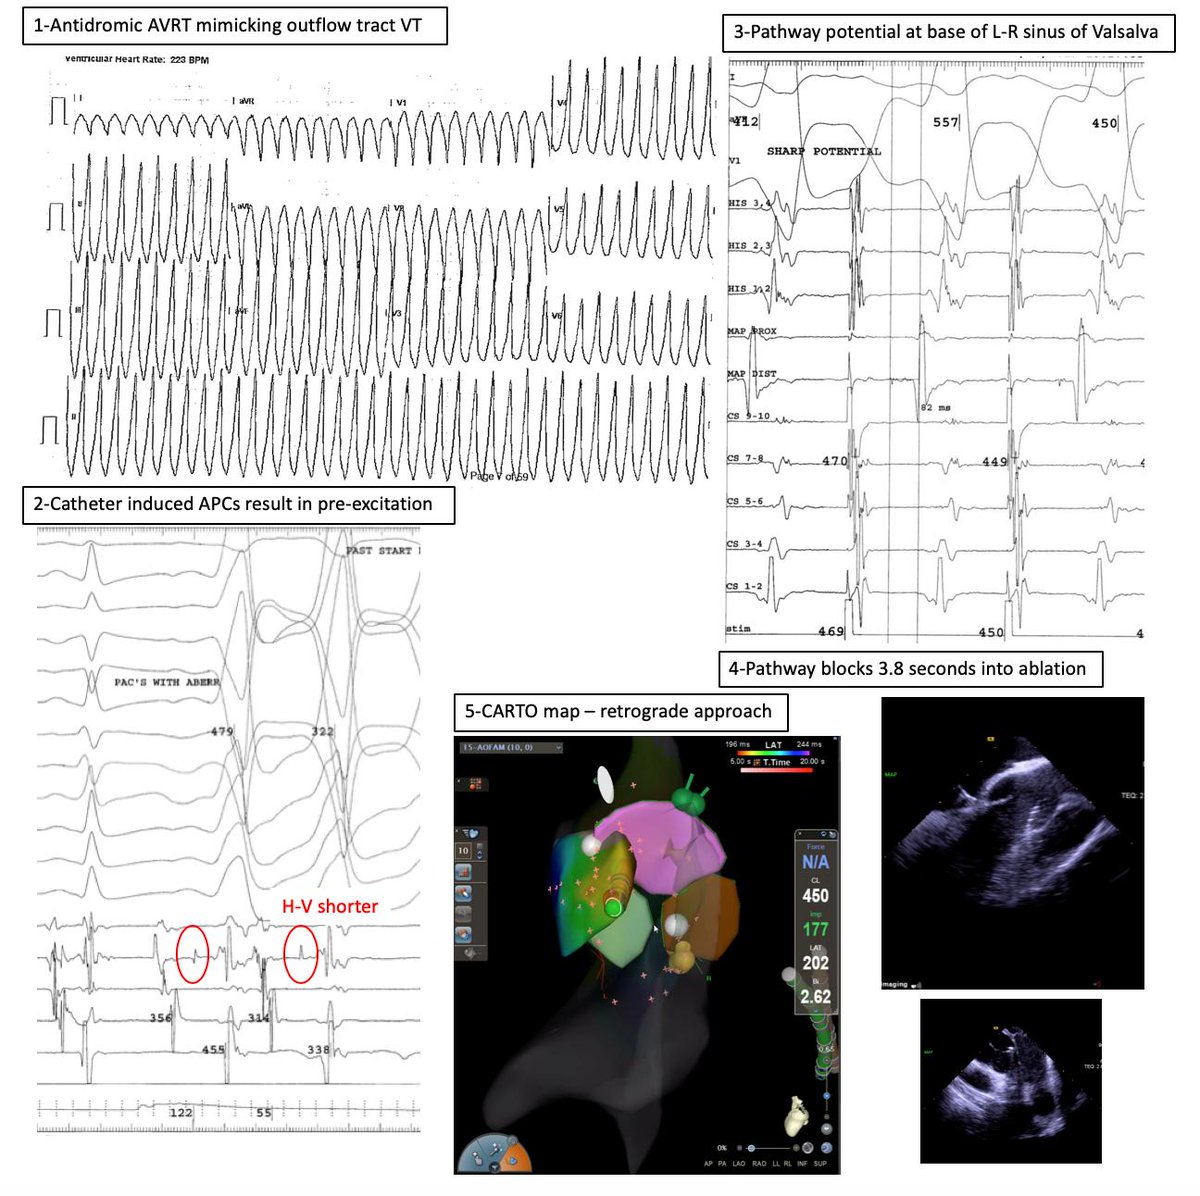

31 yo man. Antidromic ART mimicking OFT VT. Anyone seen/heard of accessory pathway to R-L SOV before? Slowly conducting and pathway potential 82 ms pre-QRS. One burn! Fun case/maneuvers. #EPPeeps @ReddyEPS @DrRigoRamirezEP @DrGregMichaud @jaymontgomery44 @DrRoderickTung @ @KUCVM

11

24

67